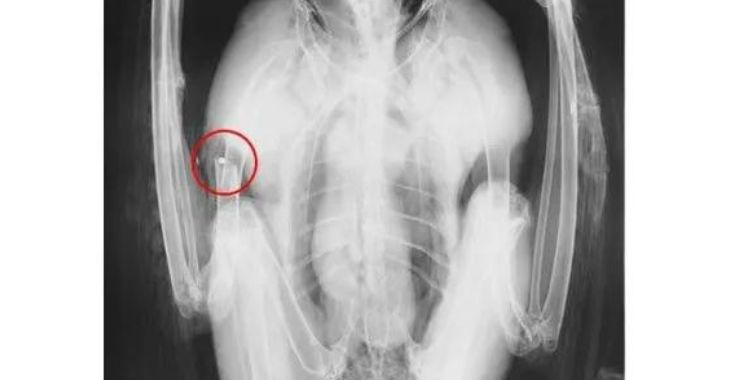

L’aigle royal a reçu au moins un plomb, entraînant une fracture ouverte de l’humérus droit. Dans la chute provoquée par ce tir, il a subi un violent choc frontal au niveau du crâne, entraînant une atteinte des deux yeux.

L’aigle a été opéré au niveau de l’aile et reste désormais sous surveillance. La Ligue de Protection des Oiseaux et le Tichodrome ont annoncé qu’ils porteraient plainte. Le rapace est le dixième oiseau d’espèce protégée à avoir été pris en charge par le centre de soins au cours de l’année 2022.